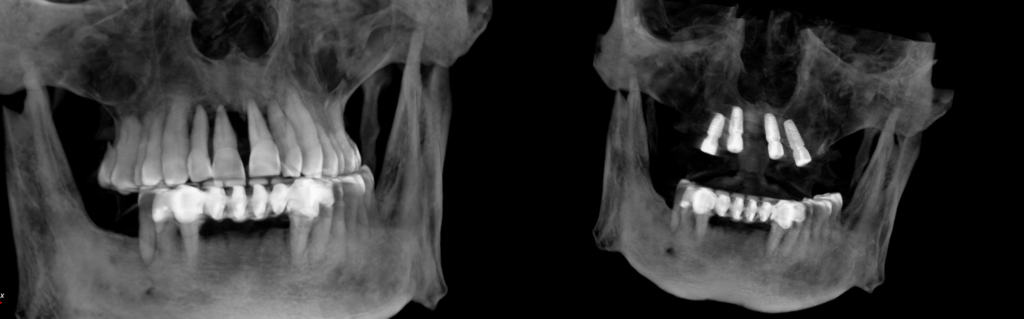

59 yaşındaki erkek hastamız, kontrol altındaki diyabetine bağlı gelişen şiddetli diş eti çekilmeleri ve buna bağlı tüm dişlerindeki ileri derece sallanma (mobilite) şikayetiyle kliniğime başvurdu. Yapılan klinik ve radyolojik değerlendirmeler sonucunda, dişlerin korunmasının mümkün olmadığı görüldü ve total dişsizlik aşamasına geçilmesini hasta ile birlikte kararlaştırdık.

İyileşme süreci tamamlandıktan sonra tamamen dijital bir iş akışı kurguladım. Hastamızın CBCT verileri ile ağız içi tarayıcıdan aldığımız dijital ölçüleri bilgisayar ortamında çakıştırdım. Guided Cerrahi (Rehberli Cerrahi) planlamasıyla implantların konumlarını, kemiğin en kaliteli olduğu noktalara göre milimetrik olarak belirledim.

Planladığımız cerrahi rehber eşliğinde operasyonu gerçekleştirdim. Bu yöntemin sağladığı hassasiyet, sadece cerrahi aşamada değil, protez aşamasında da büyük avantaj sağladı. Protez tasarım ve üretim süreçlerini de tamamen dijital tekniklerle yürüterek, ağız içi taramalar sayesinde geleneksel ölçü yöntemlerinin yarattığı konforsuzluğu ortadan kaldırdım. Hem cerrahi hem de protez aşamasındaki bu dijital entegrasyon, hata payını minimize ederek biyomekanik açıdan kusursuz bir uyum sağladı.